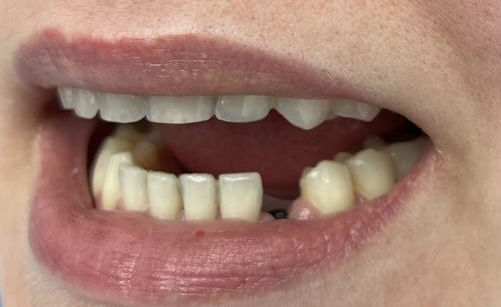

W tym przypadku zniszczonych i krótkich koron wykonano zabieg chirurgicznego wydłużenia koron klinicznych z plastyką dziąseł oraz wykonano pojedyncze korony cyrkonowe licowane porcelaną w kolorze BL2.